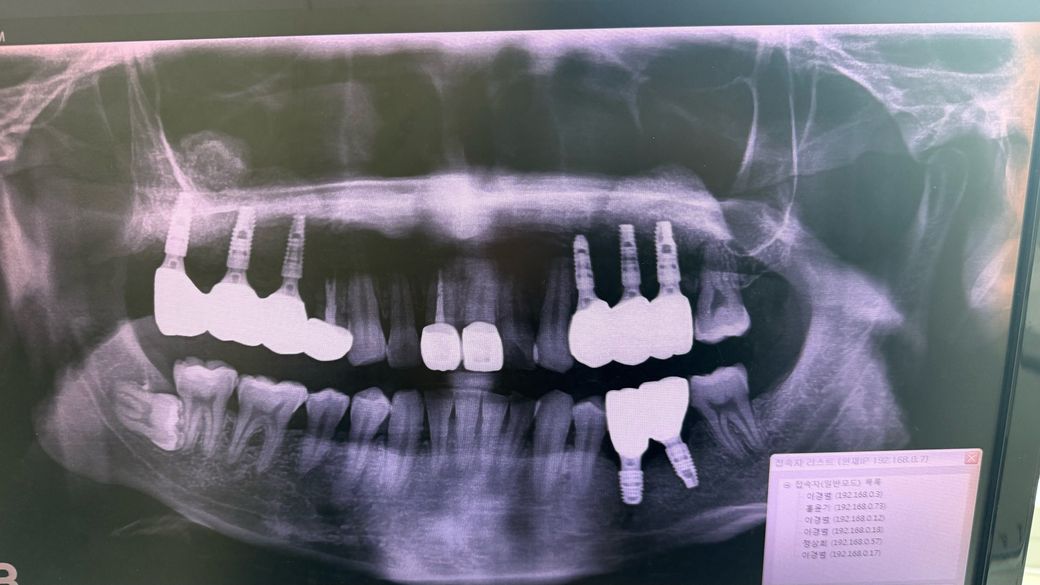

세번째 사진은 회사 근처에서 사랑니 점검 겸 파노라마 찍어왔는데 의사 선생님들의 고견을 듣고자 합니다.

• 3번 째 사진

파노라마 사진보다는 임플란트 부위 치근단 엑스레이 사진(작은 엑스레이 사진)이 좀 더 판단에 도움이 될 것 같습니다. 과거 뼈이식, 상악동 거상 후 어렵게 임플란트 심은 부위 같은데, 염증으로 인한 문제일 가능성이 높고 치과에서 적절히 조치(염증 제거)를 받으신 거면 1~2주 정도 상황을 지켜봐야 합니다. 항생제도 추가적으로 복용하시고요.